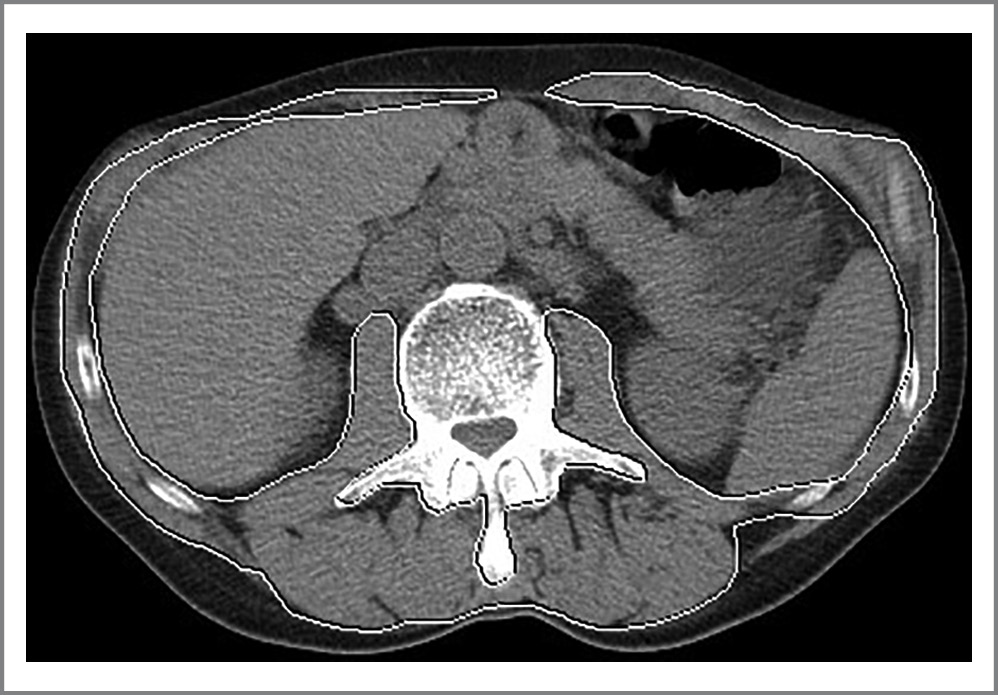

Степень послеоперационных осложнений оценивали по классификации Clavien–Dindo [9] (рис. 1).

Рис. 1. Аксиальный КТ-срез. Пациент А. КТ-саркометрия на уровне LIII позвонка до операции. Площадь выделенной зоны 130 см2, СМИ – 32 см2/м2. Саркопения.

Fig. 1. Axial CT slice. Patient A. Computed tomography sarcometry at the level of the LIII vertebra before surgery. The area of the allocated zone is 130 cm2, and the SMI is 32 cm2/m2. Sarcopenia.